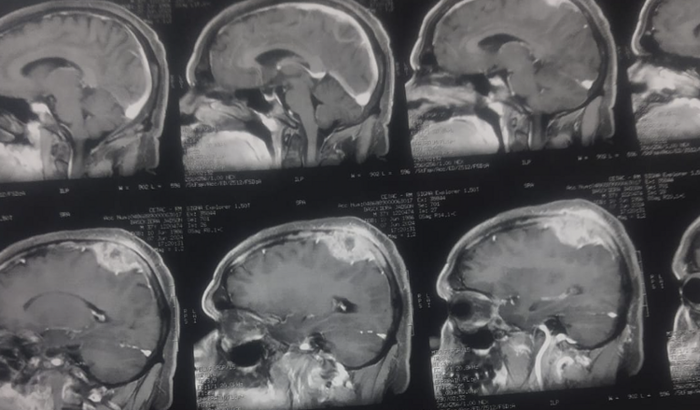

Eu sou Lucineya Maria, estou tentando fazer a cirurgia do meu márido para tentar tratar de um tumor cerebral que foi descoberto a duas semanas , eu preciso inicialmente dé R$ 2000,00 e talves precise de mais R$ 1000,00 para comprar os remédios, já tentei recorrer a amigos e vizinhos e nao consegui , então peço encarecidamente quem puder me ajudar , a cirurgia é nesta quinta agora, desde ja agradeço e que Deus Abençoe a vida de todos.